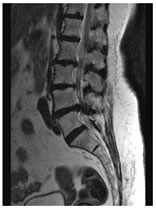

CASE 5

T1W AXIAL IMAGE SHOWING DIFFUSE DISC BULGE, LIGAMENTUM FLAVUM HYPERTROPHY AND BILATERAL FACETAL ARTHROPATHY CAUSING SEVERE THECAL SAC STENOSIS

T2W MID SAGITTAL IMAGE SHOWING MINIMAL RETROLISTHESIS OF L2 OVER L3 AND DISC DEGENERATION AT ALL LUMBER INTERVERTEBRAL LEVELS WITH REDUCED DISC HEIGHT AT FEW LEVELS. THERE IS DISC PROTRUSION NOTED AT L2-3, L3-4, L4-5 LEVELS CAUSING INDENTATION OVER THECAL SAC